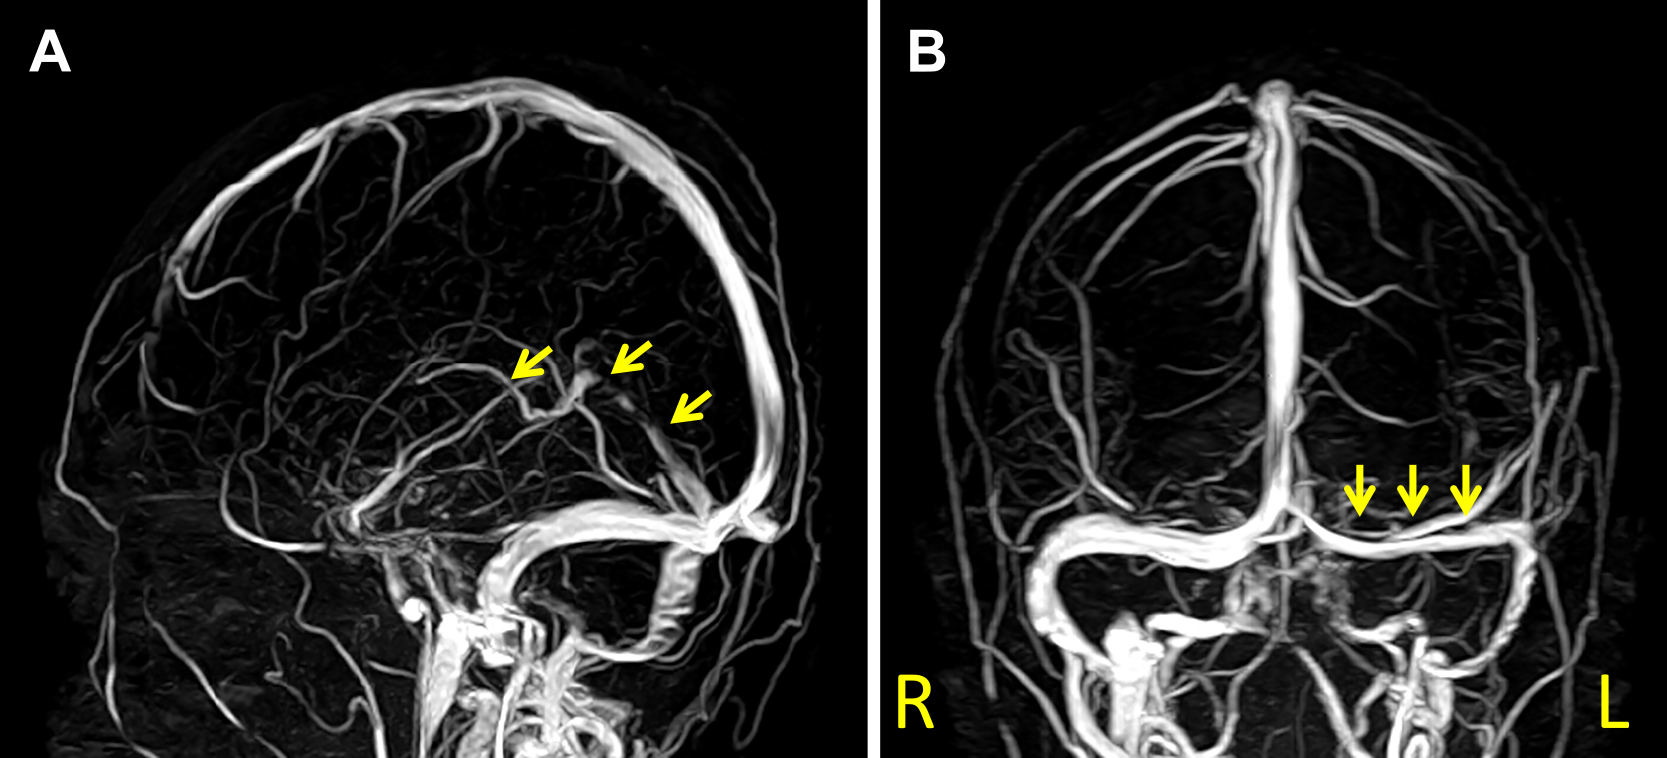

脳とその血管の画像検査は、DVST の診断に使用されます。医師は画像処理を使用して、硬膜静脈洞内の血栓を視覚化できます。

画像処理には、 CT スキャンまたはMRI スキャンが含まれます。ただし、CT または MRI 静脈造影は、DVST の診断に役立つ感度が高くなります。これらの技術では、CT スキャンまたは MRI スキャンと特別な染料の添加を使用して、静脈をより見やすくします。

CT または MRI 静脈造影検査の結果が決定的でない場合は、脳血管造影が使用されることがあります。これは、X 線と特殊な色素を使用して血管の画像を作成します。